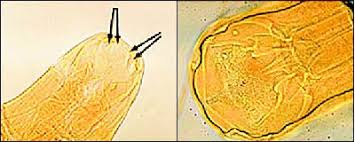

Parasite egg ascaris lumbricoides find with microscope in laboratory.

Fecal float parasite pictures gallery. Later, it can lead to heart and intestine problems. Threadworm 10 most terrifying parasites ever cbs news. If a parasite is suspected, then appropriate stool cultures (w/sensitivity testing) along with a determination of whether there are parasitic ova present should be last resort is look at pictures on the internet and find what is closest to yours and treat accordingly. I extracted a few and washed them off, i then used tweezers to squish one a answered by dr. White specks in stool causes treatment and tips. Parasites in tissue how to identify the structures cap today. Only one bot fly species attacks humans, the dermatobia hominis. Symptoms show up quickly as fever, fatigue, aches, headache, rash, loss of appetite, diarrhea, vomiting, and swollen eyelids. Pictures of parasites in human stool. Stool examination under direct smear, then microscope performed 40x magnification and show the ascaris lumbricoides fertilized egg. I think i have a parasite.? Symptoms and signs include abdominal pain, abdominal swelling, nausea, vomiting, fever, and passage of parasites and eggs in stool.